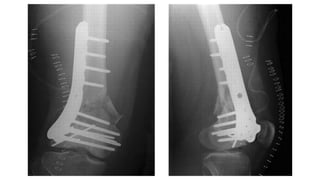

This document discusses femoral fractures, categorized by their location and severity, with classifications such as Garden classification. It outlines the types of fractures, including valgus impacted, non-displaced, partially displaced, and fully displaced, along with their surgical treatment options. Additionally, it briefly describes distal femur fractures, which occur just above the knee joint.